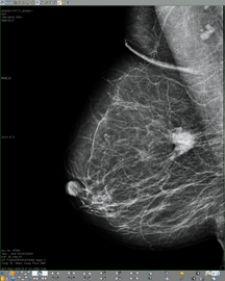

Candelis received 510(k) marketing clearance for its ImageGrid Mammography Web Viewer and ImageGrid Radiology Web Viewer, both now part of the ImageGrid RIS/PACS appliance technology suite, providing diagnostic tools aimed at providing access to medical imaging studies from anywhere, at any time to improve patient care.

The ImageGrid Mammography Web Viewer and Radiology Web Viewer applications are said to be highly scalable and designed to accommodate multiple concurrent users without the need to invest in additional servers. As a multimodality visualization solution, the viewers allow radiologists to view all relevant prior studies from one workstation.